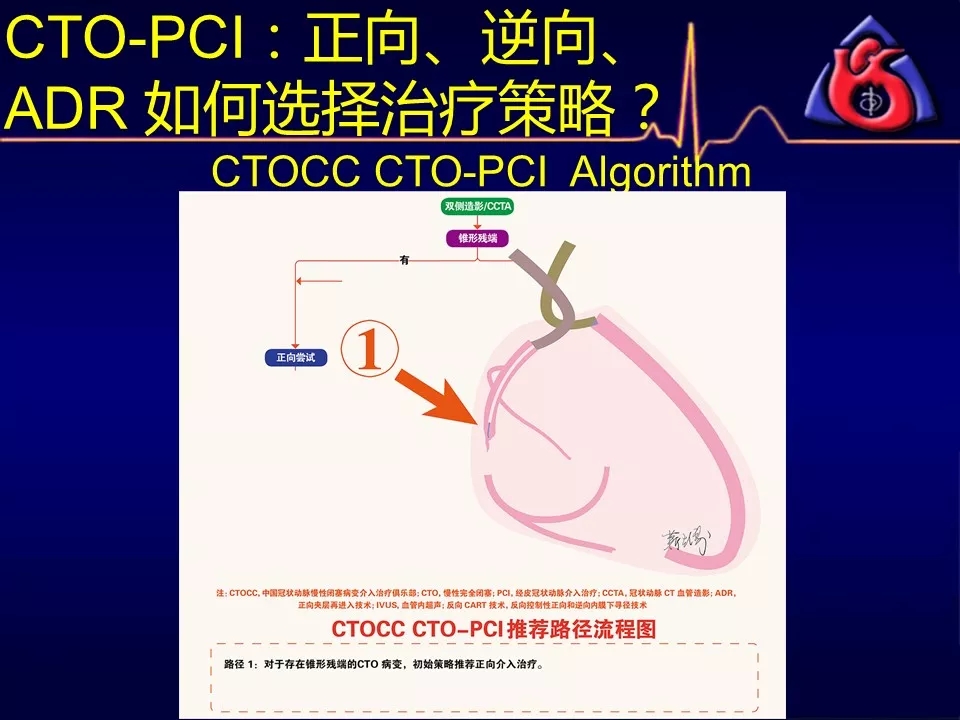

学习CTOCC CTO-PCI流程图的你

一定有此疑惑:

如何选择正向、逆向、IVUS指引及ADR技术?

别着急,葛雷教授带来动态幻灯版讲座:

《CTOCC CTO-PCI流程图精讲》

为您解答上述疑问

PS:本篇为第一部分